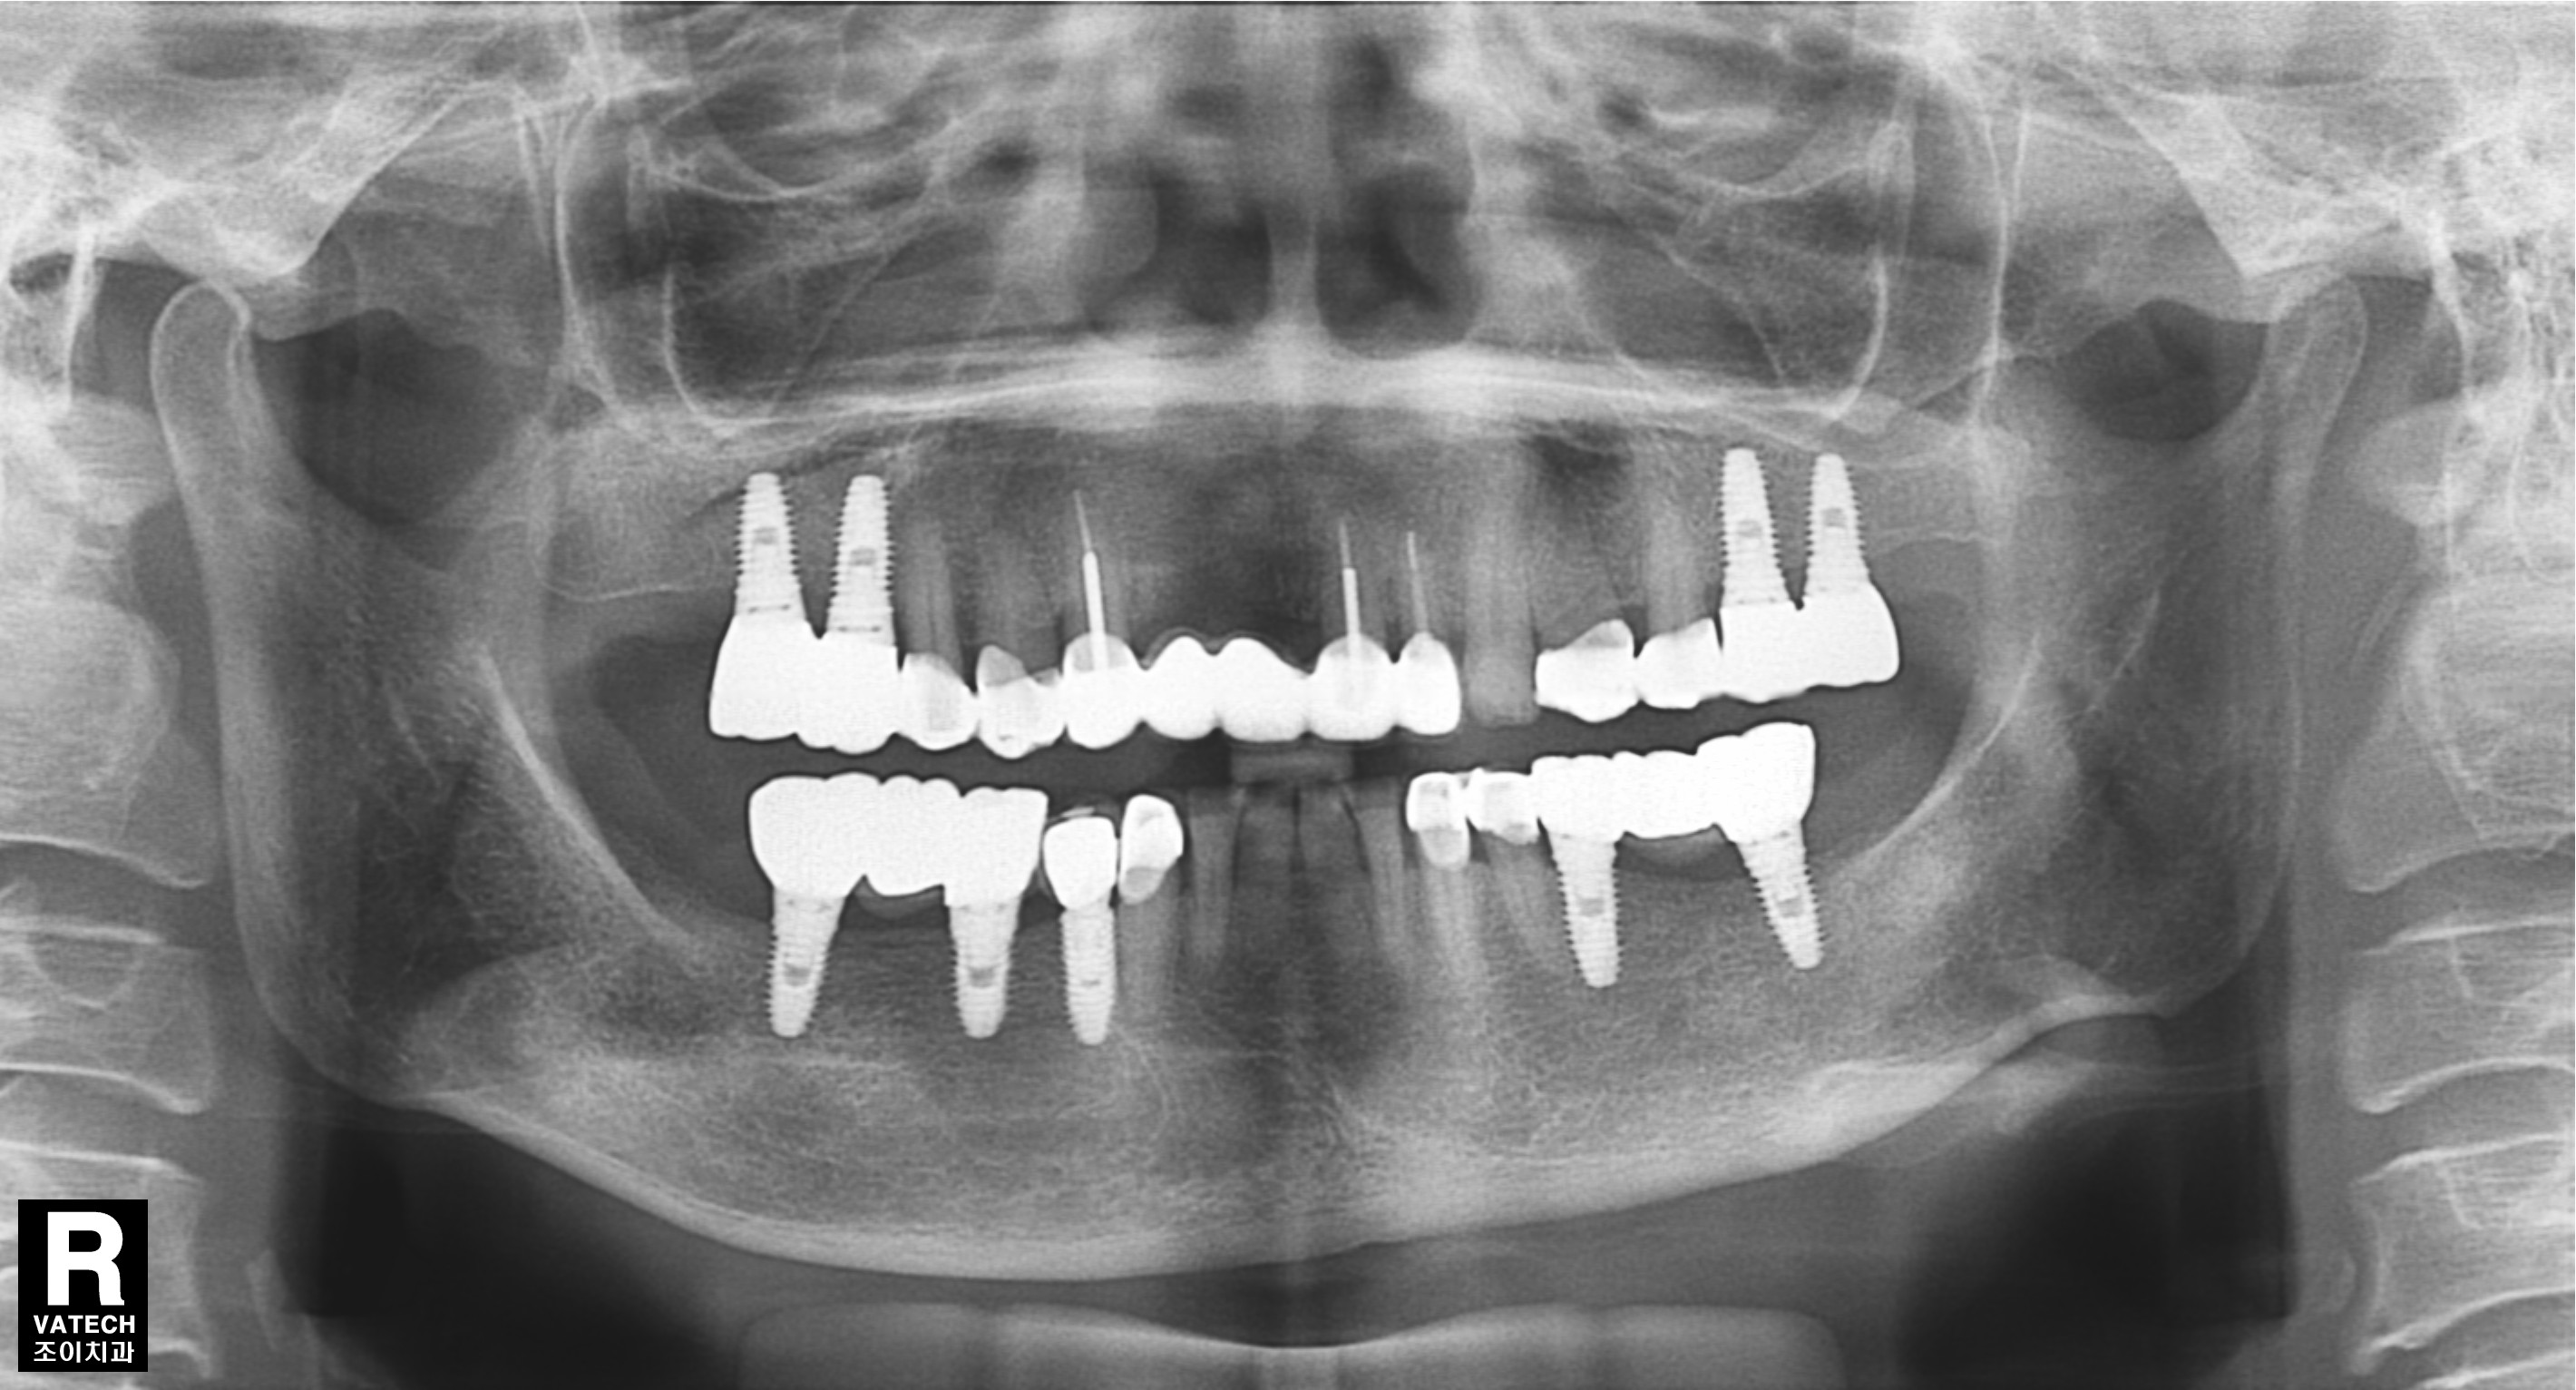

초진과 임플란트 보철 완성 직후 그리고 7년 경과 후 사진의 비교입니다.

또한 임플란트의 사용과 유지 관리에 있어서도 반드시 정기적으로 치과를 방문하여 적절한 관리를 받아야 합니다. 사진에서는 7년이 경과한 후에도 치조골의 흡수 없이 잘 유지되고 있는 상태를 관찰할 수 있습니다.